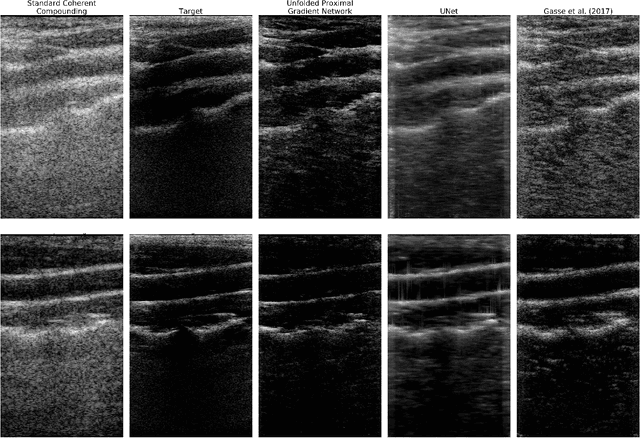

Abstract:Plane Wave imaging enables many applications that require high frame rates, including localisation microscopy, shear wave elastography, and ultra-sensitive Doppler. To alleviate the degradation of image quality with respect to conventional focused acquisition, typically, multiple acquisitions from distinctly steered plane waves are coherently (i.e. after time-of-flight correction) compounded into a single image. This poses a trade-off between image quality and achievable frame-rate. To that end, we propose a new deep learning approach, derived by formulating plane wave compounding as a linear inverse problem, that attains high resolution, high-contrast images from just 3 plane wave transmissions. Our solution unfolds the iterations of a proximal gradient descent algorithm as a deep network, thereby directly exploiting the physics-based generative acquisition model into the neural network design. We train our network in a greedy manner, i.e. layer-by-layer, using a combination of pixel, temporal, and distribution (adversarial) losses to achieve both perceptual fidelity and data consistency. Through the strong model-based inductive bias, the proposed architecture outperforms several standard benchmark architectures in terms of image quality, with a low computational and memory footprint.